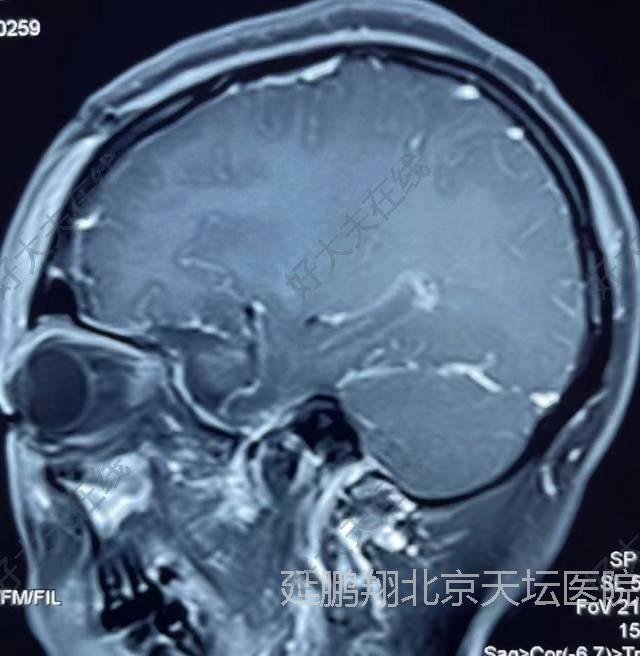

治疗中

手术在全麻下进行,釆用左额颞入路,先切断肿瘤基底,阻断血供。肿瘤质地软,与脑组织粘连不紧,易分离,两者相隔有蛛网膜(图2),肿瘤切除后左侧嗅神经,视神经,颈内动脉,动眼神经均保护完好(图3)。